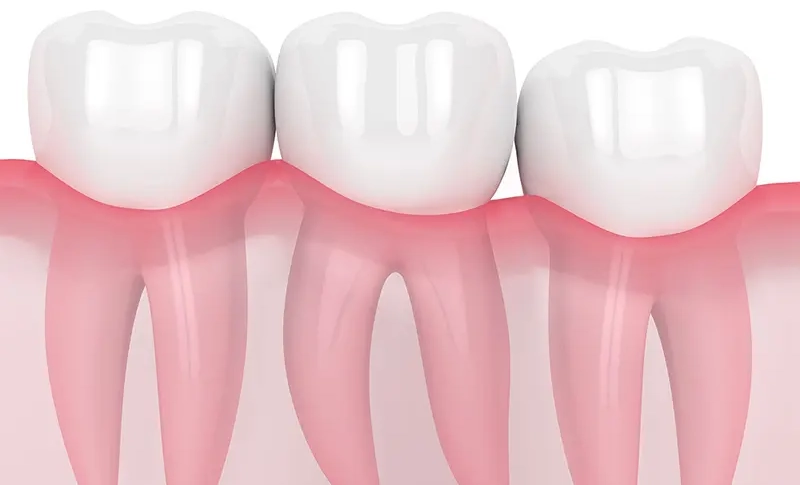

親知らずとは?

親知らずとは、上下左右の一番奥に生える永久歯のことで、一般的に10代後半から20代前半にかけて生えてきます。

しかし、生える時期や方向には個人差があり、近年ではあごが小さい方が増えているため、まっすぐ生えるスペースが不足していることもあります。